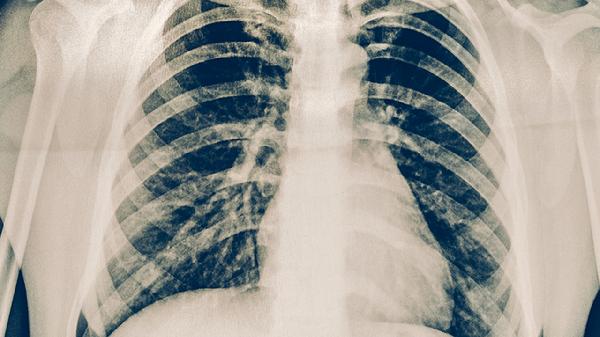

肺癌患者需遵医嘱使用吉非替尼片、盐酸厄洛替尼片、注射用培美曲塞二钠、卡铂注射液、盐酸安罗替尼胶囊等药物。肺癌的治疗药物选择需根据病理类型、分期及基因检测结果综合决定,不同药物针对的靶点与适应症存在差异,患者不可自行用药。

肺癌患者除规范用药外,应保持高蛋白、高热量饮食以改善营养状态,适量补充维生素D和抗氧化营养素。避免吸烟及二手烟暴露,根据体力进行散步、太极拳等低强度运动。治疗期间每3个月复查胸部CT,出现咯血、持续性胸痛等症状需及时返院评估。心理疏导与疼痛管理对提高生活质量同样重要,家属应协助患者建立规律作息并记录用药反应。